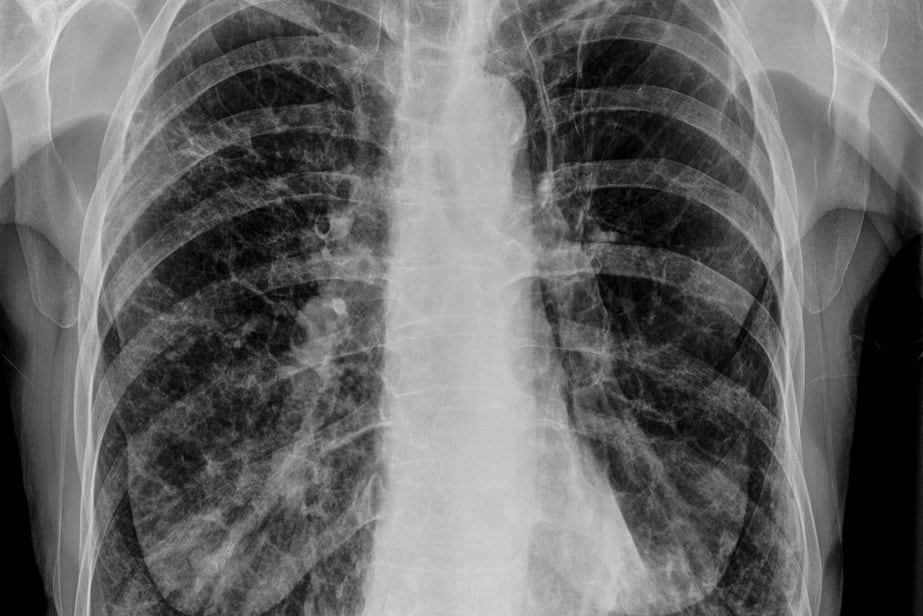

La Enfermedad Pulmonar Obstructiva Crónica (EPOC) tiene un alto nivel de subdiagnóstico y desde la Asociación Argentina de Medicina Respiratoria (AAMR) estiman que el 70% de las personas